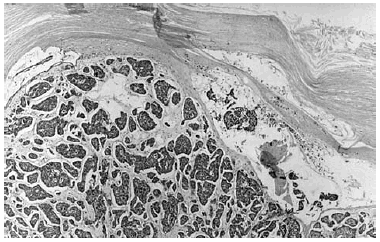

Se realizó una biopsia amplia de la lesión, incluyendo la tumoración nodular. En el examen histopatológico se podía observar una epidermis eosinófila, con una desestructuración que afectaba todo su espesor, ocupada en todo su grosor por queratinocitos atípi-cos con frecuentes mitosis, la mayoría de ellas atípicas. En el estrato córneo había hiperqueratosis, con áreas de paraqueratosis. En dermis superficial existía un infiltrado inflamatorio crónico en banda formado predominantemente por linfocitos con algún histiocito aislado (fig. 2).

Fig. 2.--Alteración de todo el espesor de la epidermis circundante, con paraqueratosis, células disqueratósicas y mitosis.

La zona correspondiente al nódulo ulcerado se correspondía con una lesión tumoral de color basófilo, que en su superficie presentaba continuidad con la epidermis y estaba en parte ulcerada. La tumoración ocupa la dermis, llegando en profundidad hasta el tejido celular subcutáneo (fig. 3) y estaba compuesta por nidos y cordones de células epiteliales muy anaplásicas, con núcleos vesiculosos y citoplasma escaso, con frecuentes monstruosidades celulares y alto índice de mitosis, siendo muchas de ellas atípicas (fig. 4). El diagnóstico fue de carcinoma espinocelular basaloide invasivo (Bowen invasivo).

Fig. 3.--Aspecto de la lesión nodular invasiva formada por nódulos basaloides.

En la histología se observa la presencia de un carcinoma in situ tipo Bowen en la epidermis circundante y un tumor dérmico invasivo compuesto por grandes islotes de células generalmente basaloides y escamosas, y ocasionalmente con áreas de necrosis central y retracción periférica artefacta, lo que recuerda al patrón visto en el carcinoma de células basales metatípico. La diferenciación escamosa es el patrón de diferenciación más frecuente. La diferenciación basaloide y la basoescamosa son hallazgos también frecuentes. Los patrones de pobre diferenciación o diferenciación pilar o pilosebácea son raros. Raramente se observa diferenciación glandular. Estos datos histológicos hacen que a menudo el patólogo tenga una impresión de estar ante un carcinoma anexial con diferenciación pilar, un carcinoma sebáceo, un carcinoma de glándula ecrina o un adenocarcinoma metastásico. Por estos motivos el diagnóstico puede ser difícil de establecer cuando la evidencia de enfermedad de Bowen en la epidermis circundante esté ausente en los cortes disponibles17.